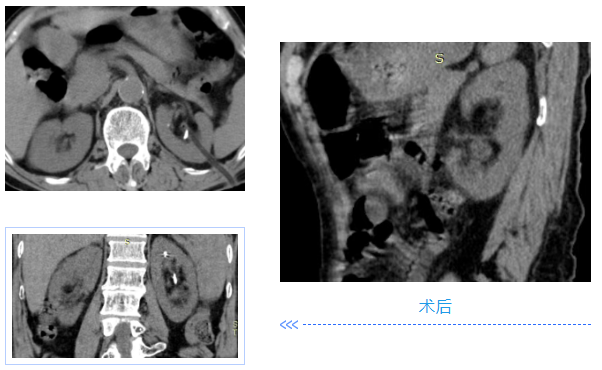

两名患者均为中年男性,入院检查发现肾内多发铸型结石,结石体积大、分布广,其中一例既往患肾行开放取石及经皮肾取石手术,盏颈狭窄伴有肾积水;另一例无明显积水,净石难度高。传统开放手术创伤大、恢复慢,单一微创技术难以彻底清除结石。针对患者病情,泌尿外科团队高度重视,多次组织病例讨论,结合患者身体状况与手术耐受度,最终制定“经皮肾镜+输尿管软镜”联合微创治疗方案。

在泌尿外科团队及麻醉科团队成员密切配合。患者取斜仰截石位,先通过输尿管软镜探查输尿管及肾盂肾盏情况,精准定位结石;随后在超声引导下建立经皮肾通道,置入经皮肾镜,利用钬激光碎石设备将复杂结石击碎成细小颗粒,部分结石因角度问题经皮肾镜无法够到,则通过软镜配合取石篮将结石拖入经皮肾通道口进行彻底清除。整个手术过程创伤小、出血少,术后患者恢复顺利,未出现相关并发症,现已康复出院。